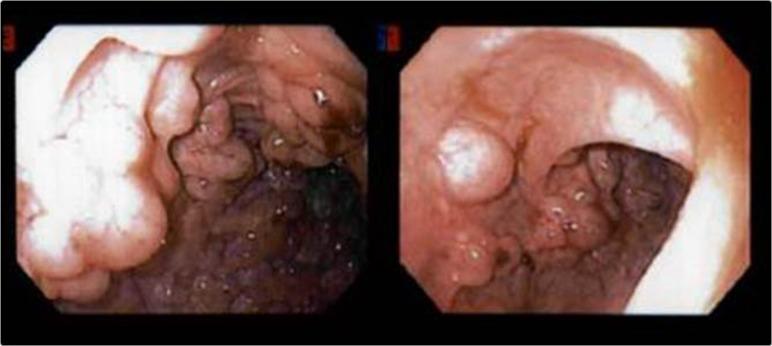

This is a case of a 54-year-old gentleman who presented to an outside hospital emergency department with lower abdominal pain. Computed tomography imaging showed a small amount of intraperitoneal free air and cystic pneumatosis coli. He was admitted, managed conservatively with intravenous antibiotics, and then discharged home after his symptoms improved. Elective laparoscopic sigmoid colectomy was subsequently performed with intraoperative findings of partial sigmoid volvulus and extensive pneumatosis coli of the sigmoid colon. Pneumoperitoneum was determined to be from ruptured intramural cysts. The etiology of pneumatosis coli was likely from chronic sigmoid volvulus.

这是一名54岁男性患者的病例,他因下腹部疼痛前往外院急诊科就诊。计算机断层扫描成像显示腹腔内有少量游离气体和结肠囊样积气。他入院后接受了静脉抗生素保守治疗,症状改善后出院。随后进行了择期腹腔镜乙状结肠切除术,术中发现部分乙状结肠扭转和乙状结肠广泛积气。确定气腹是由壁内囊肿破裂所致。结肠积气的病因可能是慢性乙状结肠扭转。